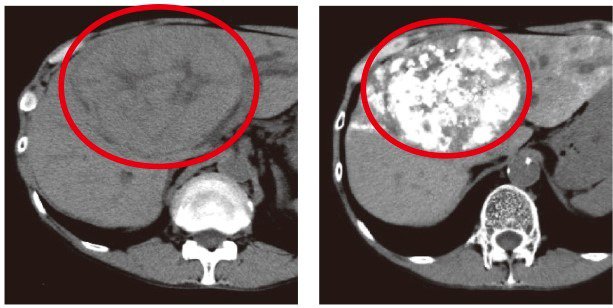

万が一腫瘍が見つかった場合は、造影CT検査や造影MRI検査を行います。CTは被ばくのリスクがありますが、通常の検査では被ばくの影響が少なく、当院のCTは通常より被ばく量を低減する装置も常備されています。MRIはCTに比べて検査時間が長くなりますが、CTと違って被ばくの心配はなく、CTよりも早期の肝がんを発見しやすいといわれています。

肝がんと診断された場合、主な治療法には消化器外科が担当する「手術」と、消化器内科の分野である「経皮的穿刺治療(主にラジオ波焼灼術)」「血管造影(主に肝動脈塞栓術)」「化学療法」の4つがあり、必要に応じて外科・内科・放射線科が連携しながら治療に当たります。特に当院の経皮的穿刺治療と血管造影は、全国トップ水準かつ体に負担の少ない治療を行える環境が整っています。